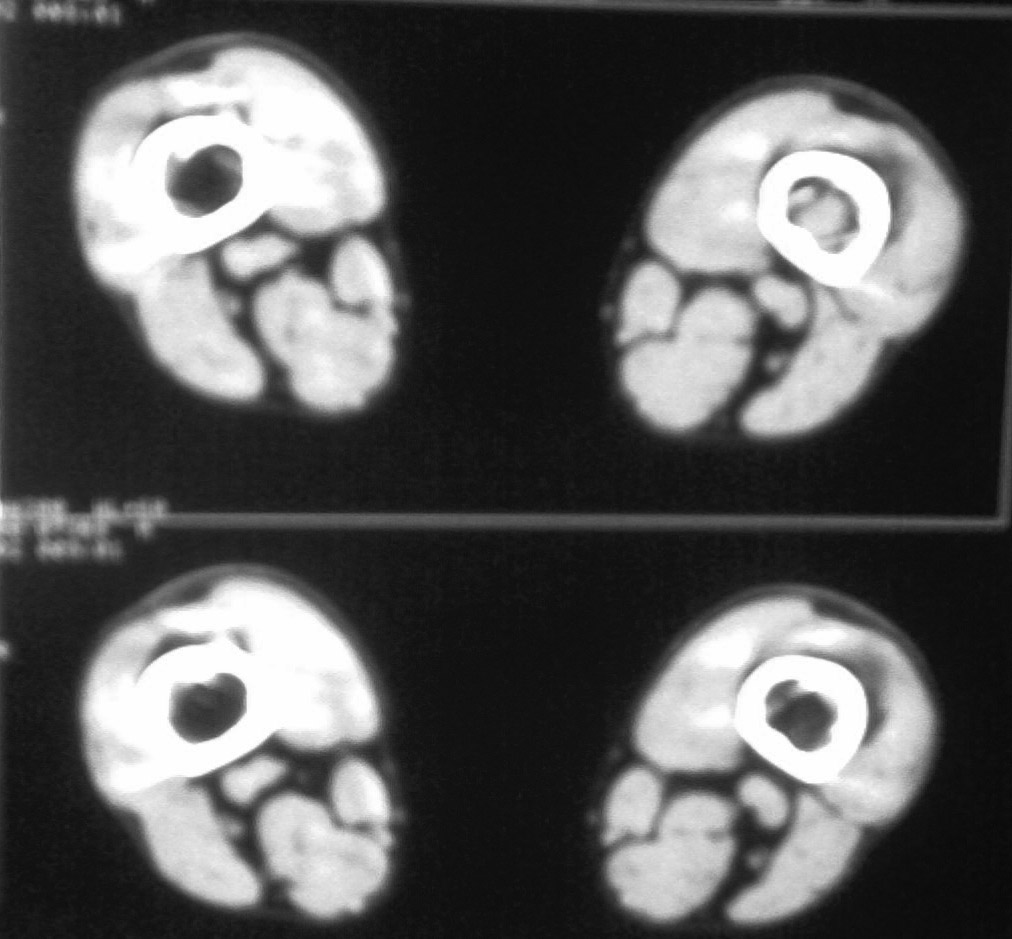

标题: CT17838:F20Y,右肱骨痛疼一年余 [打印本页]

标题: CT17838:F20Y,右肱骨痛疼一年余

ct看起来只是髓腔内钙化,皮质无破坏,与下面的平片不大同,不知为甚?